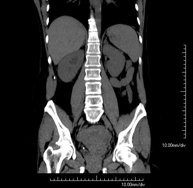

- TC Abdominopélvico Prueba diagnóstica que consiste en obtener imágenes bi y tridimensionales del abdomen y de la pelvis de alta definición anatómica (estructuras óseas, estructuras vasculares, hígado, páncreas, vesícula biliar, riñones, glándulas suprarrenales, bazo, intestino delgado y grueso, vejiga, útero y ovarios, próstata y vesículas seminales, uréteres, etc.) mediante el empleo de un equipo de TC (Tomografía Computarizada). La mayoría de estudios requieren el empleo de contraste yodado. Prueba diagnóstica que consiste en obtener imágenes bi y tridimensionales del abdomen y de la pelvis de alta definición anatómica (estructuras óseas, estructuras vasculares, hígado, páncreas, vesícula biliar, riñones, glándulas suprarrenales, bazo, intestino delgado y grueso, vejiga, útero y ovarios, próstata y vesículas seminales, uréteres, etc.) mediante el empleo de un equipo de TC (Tomografía Computarizada). La mayoría de estudios requieren el empleo de contraste yodado.